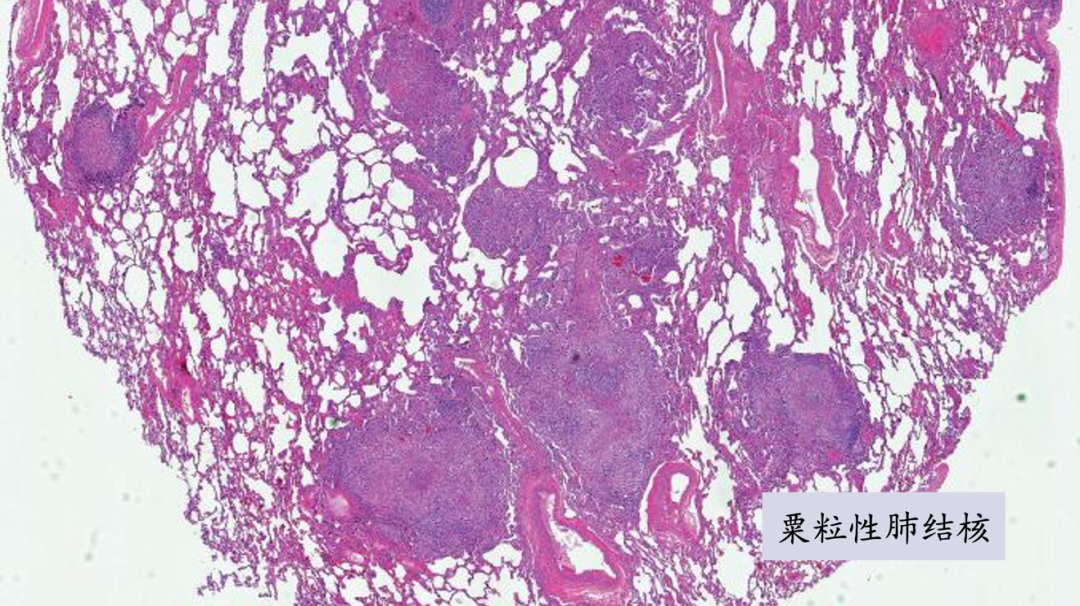

下图是一个粟粒性肺结核的病理切片。肺组织里无数个小结节,结节的中央是干酪样坏死,周围上皮样组织细胞,高倍镜下可见朗格罕多核巨细胞。

朗格罕多核巨细胞实际上是多个组织细胞融合在一起,其细胞核排列像马蹄状: